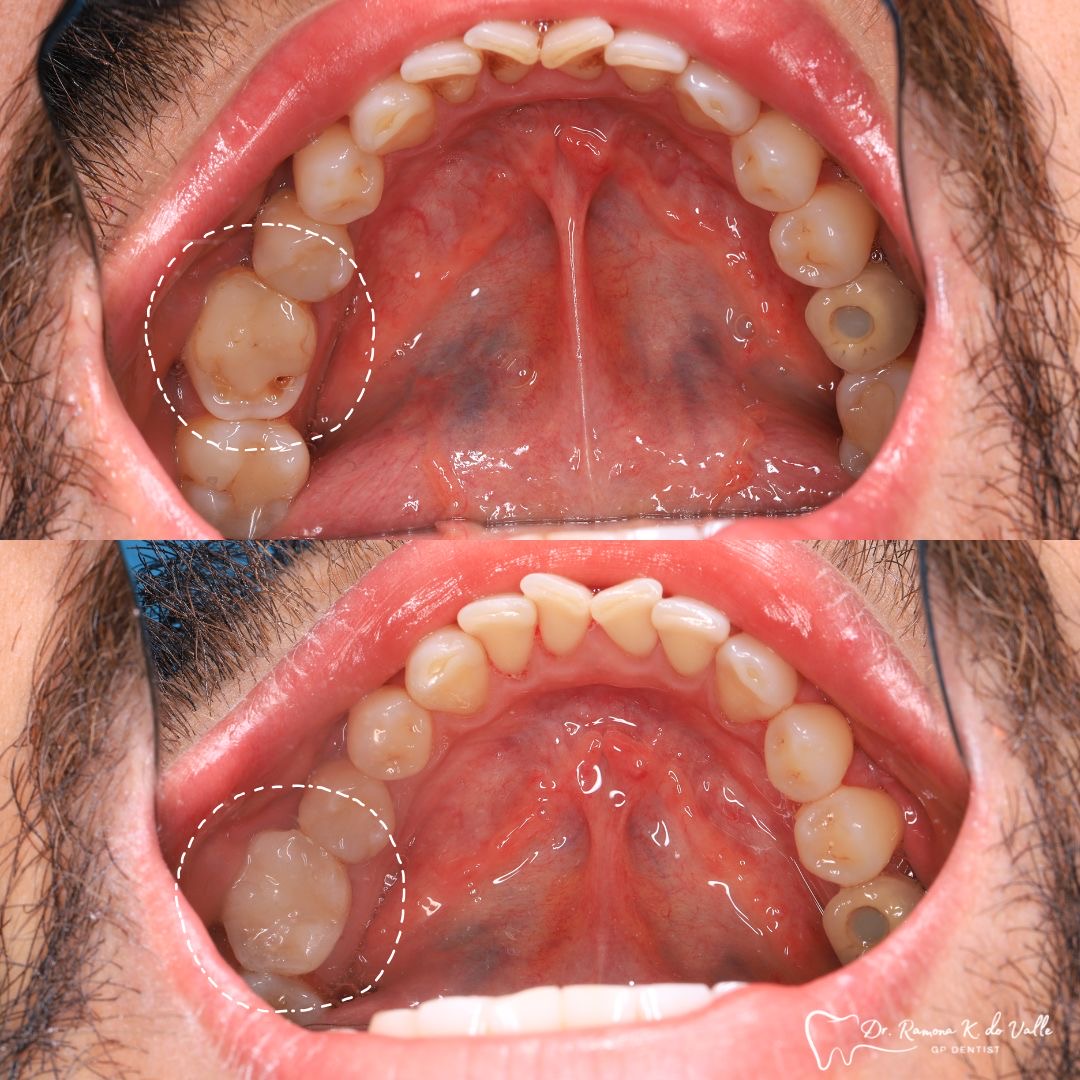

• replacing old metal fillings with a tooth-coloured option

The tooth-coloured resin is applied in thin layers and shaped carefully to match natural anatomy. For front-tooth work, we may combine several shades for a lifelike result.

We remove weakened or decayed tissue and clean the area thoroughly. The goal is to preserve as much healthy structure as possible.